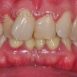

Interdisciplinary Treatment of Patients with Deep Overbite and Parafunctional Activity

Bruxism is defined as parafunctional grinding of teeth and due to the excessive wear of the posterior teeth, patients with long-standing bruxism often have pathological deep overbite. For many decades, treatment of bruxism and deep overbite was focused on reshaping the bite for achieving an occlusion free of deviations. Despite large efforts, the management of bruxism and subsequent deepening overbite was not obtained.